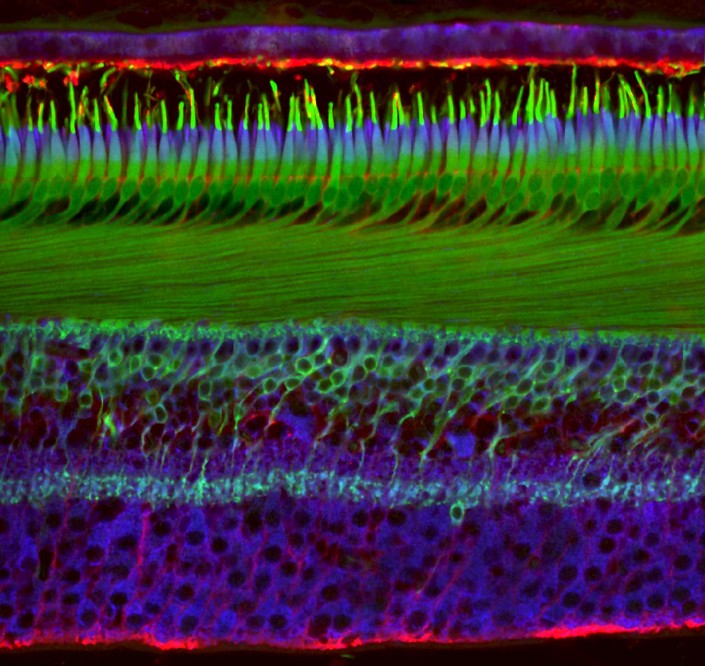

20-е место. Сетчатка глаза человека, 40-кратное увеличение.

Николас Куэнка и Изабель Ортуньо-Лизаран, Университет Аликанте, Испания